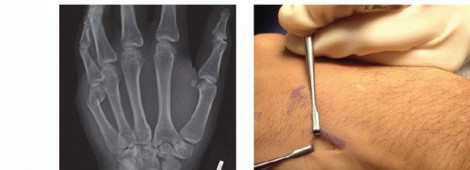

Standard radiographic imaging forms the cornerstone of diagnostic evaluation, requiring, at minimum, a dedicated posteroanterior (PA), a true lateral, and a pronated oblique view of the injured hand. The PA view is excellent for assessing coronal plane angulation and transverse displacement, though it notoriously underestimates sagittal plane deformity. The true lateral view is critical for quantifying apex-dorsal angulation, though overlapping metacarpal shadows can complicate interpretation. The pronated oblique view often provides the clearest visualization of the fracture profile and the degree of comminution.

Percutaneous and Intramedullary Techniques

For transverse or short oblique fractures of the metacarpal neck and shaft, particularly in the fifth metacarpal, percutaneous or minimally invasive intramedullary techniques offer excellent stability while sparing the dorsal soft-tissue envelope. The procedure begins with a closed reduction utilizing the Jahss maneuver: the MCP and PIP joints are flexed to 90 degrees, relaxing the intrinsic muscles and tightening the collateral ligaments, allowing the proximal phalanx to be used as a lever to push the metacarpal head dorsally, correcting the apex-dorsal angulation.

Once reduced, fixation can be achieved via crossed Kirschner wires or retrograde intramedullary pinning (the "bouquet" technique). However, the modern gold standard for minimally invasive fixation is the retrograde intramedullary headless compression screw. A small stab incision is made over the dorsal aspect of the flexed MCP joint. The entry portal is meticulously established in the articular "safe zone" of the metacarpal head—specifically the dorsal-ulnar or dorsal-radial collateral recess, strictly avoiding the central weight-bearing articular cartilage.

A guidewire is advanced down the medullary canal across the fracture site under fluoroscopic guidance. After confirming perfect rotational alignment and length, the canal is sequentially broached or drilled, and an appropriately sized headless compression screw is buried beneath the articular cartilage. This technique provides robust, load-sharing stability that allows for immediate, unrestricted active range of motion, vastly reducing the incidence of postoperative stiffness compared to traditional K-wire constructs.